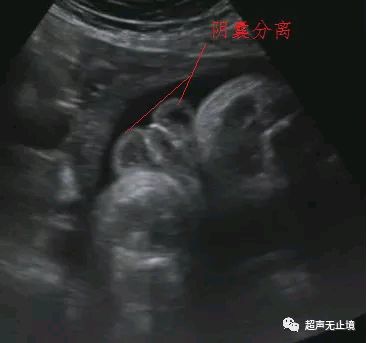

“郁金香征”为胎儿严重尿道下裂表现,代表短小弯曲的阴茎位于分裂的阴囊之间